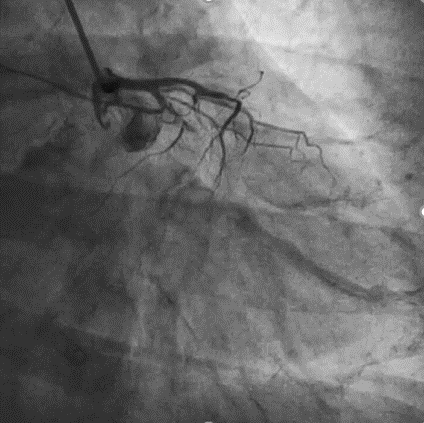

手术影像

左冠优势,LM、LCX未见狭窄,TIMI3级;LAD近段CTO,TIMI0级

RCA细小,近中段狭窄40%-50%,TIMI3级;远端可见LAD侧枝血流

策略讨论:近端纤维帽不清晰,LAD中段显影可见,闭塞段长度>20mm。间隔支逆供条件尚可。CTA提示LAD多发钙化。尝试正向开通,优选亲水性滑导丝,若失败,及时调整逆向策略。